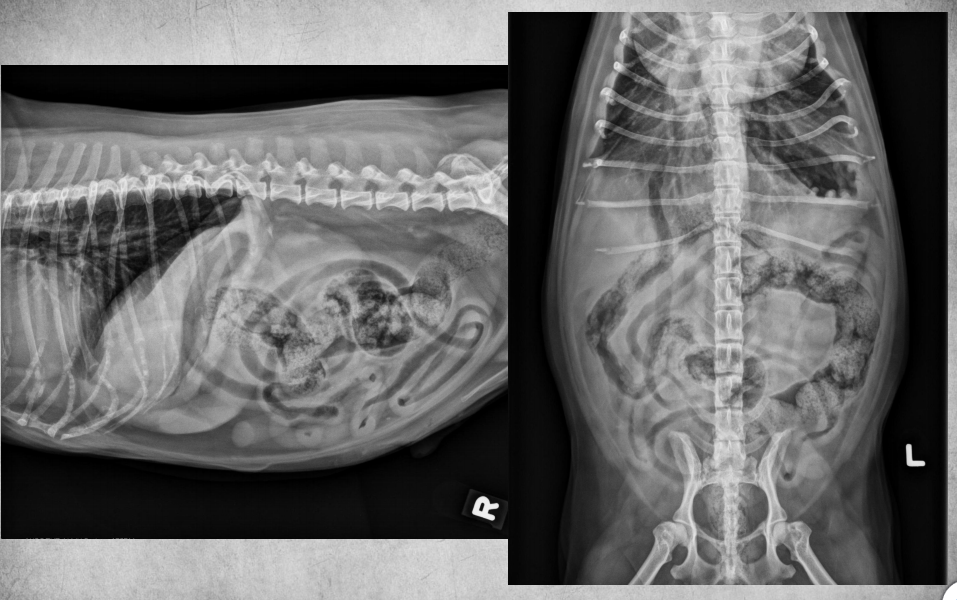

● 12 yo male castrated Shih-Tzu

● Geriatric check-up

● No clinical signs

congenital peritoneal-pericardial diaphragmatic hernia

these intestines are filled with gas due to

being empty

gastric axis also altered